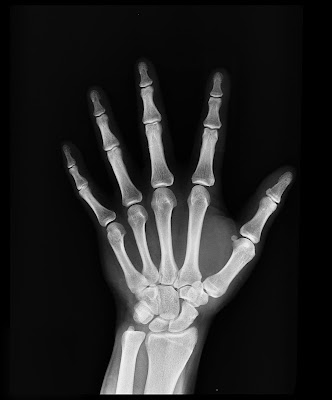

1) Surgery - X-Rays can pass through flesh and not through bones. They are of extensive use in Surgery to detect fractures, foreign bodies diseased organs etc. The patient is made to stand between an X-Ray source and a fluorescent screen.

The luminosity of the screen depends upon the stopping power of different parts of the body. Thus a depe shadow of the bones and a light shadow of the flesh will be obtained. It is called radiograph. If the various parts do not show sufficient contrast, artificial means are adopted e.g., in radiographing the portions of the alimentary tract, the patient is fed with a meal of barium sulphate.